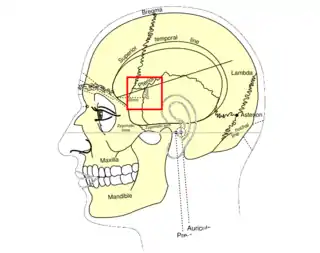

Vista lateral de la cabeza, mostrando las relaciones superficiales de huesos. El pterion está marcado en el centro. | ||